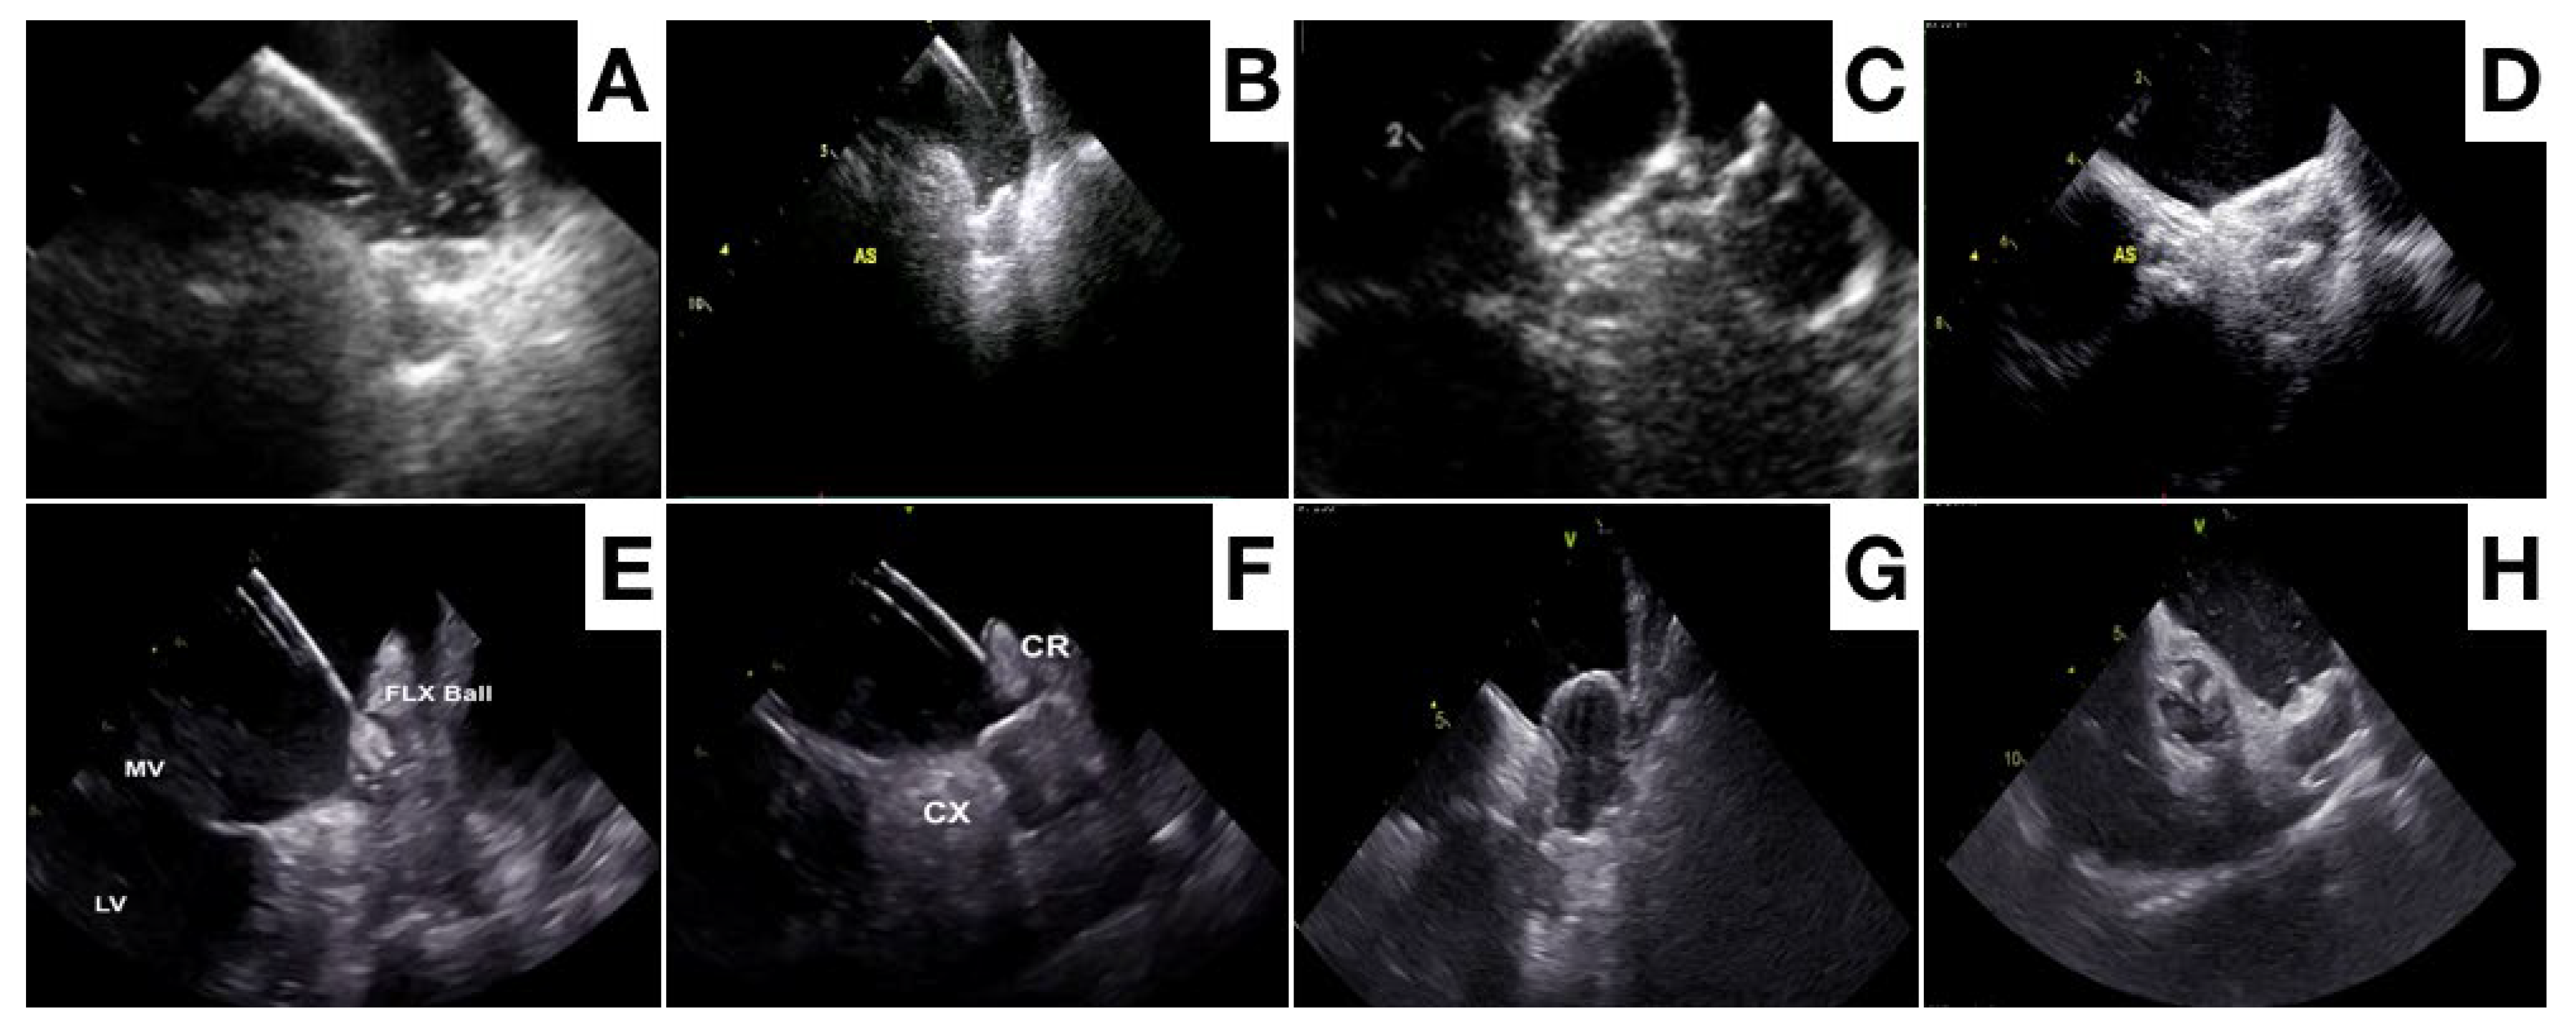

- Berti, S.; Pastormerlo, L.E.; Santoro, G.; Brscic, E.; Montorfano, M.; Vignali, L.; Danna, P.; Tondo, C.; Rezzaghi, M.; D’Amico, G.; et al. Intracardiac Versus Transesophageal Echocardiographic Guidance for Left Atrial Appendage Occlusion: The LAAO Italian Multicenter Registry. JACC Cardiovasc. Interv. 2018, 11, 1086–1092. [Google Scholar] [CrossRef] [PubMed]

- Nielsen-Kudsk, J.E.; Berti, S.; De Backer, O.; Aguirre, D.; Fassini, G.; Cruz-Gonzalez, I.; Grassi, G.; Tondo, C. Use of Intracardiac Compared With Transesophageal Echocardiography for Left Atrial Appendage Occlusion in the Amulet Observational Study. JACC Cardiovasc. Interv. 2019, 12, 1030–1039. [Google Scholar] [CrossRef] [PubMed]

- Alkhouli, M.; Chaker, Z.; Alqahtani, F.; Raslan, S.; Raybuck, B. Outcomes of Routine Intracardiac Echocardiography to Guide Left Atrial Appendage Occlusion. JACC Clin. Electrophysiol. 2020, 6, 393–400. [Google Scholar] [CrossRef]

- Ribeiro, J.M.; Teixeira, R.; Puga, L.; Costa, M.; Gonçalves, L. Comparison of intracardiac and transoesophageal echocardiography for guidance of percutaneous left atrial appendage occlusion: A meta-analysis. Echocardiography 2019, 36, 1330–1337. [Google Scholar] [CrossRef] [PubMed]

- Nielsen-Kudsk, J.E.; Berti, S.; Caprioglio, F.; Ronco, F.; Arzamendi, D.; Betts, T.; Tondo, C.; Christen, T.; Allocco, D.J. Intracardiac Echocardiography to Guide Watchman FLX Implantation: The ICE LAA Study. JACC Cardiovasc. Interv. 2023, 16, 643–651. [Google Scholar] [CrossRef]

- Alkhouli, M.; Simard, T.; El Shaer, A.; Bird, J.; Nkomo, V.T.; Freidman, P.A.; Thaden, J.; Padang, R. First Experience With a Novel Live 3D ICE Catheter to Guide Transcatheter Structural Heart Interventions. JACC Cardiovasc. Imaging. 2022, 15, 1502–1509. [Google Scholar] [CrossRef]